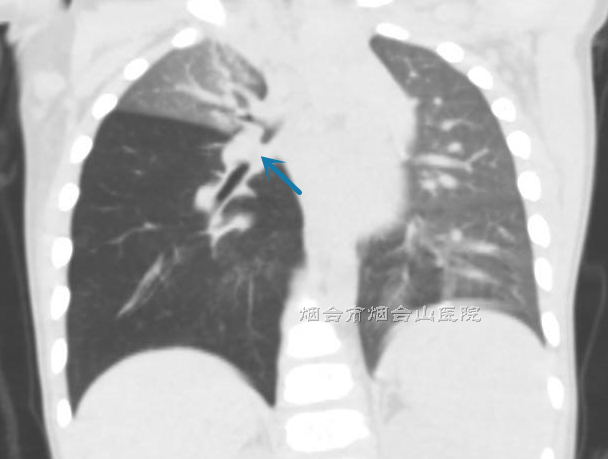

待询问病史,做了相应检查后,医生初步判断桐桐的气道内有异物,需要应用支气管镜探查并取出异物。当时距吸入异物已有4天,且花生米这样的异物极易引发患儿气道内粘膜肉芽组织增生,这些都给支气管镜探查并取出异物带来了难度。术前检查显示,桐桐的右肺中间干支气管管腔被肉芽组织及异物充填,导致其下各叶段的肺部出现肺气肿。

检查显示,桐桐的右肺中间干支气管管腔被肉芽组织及异物充填。